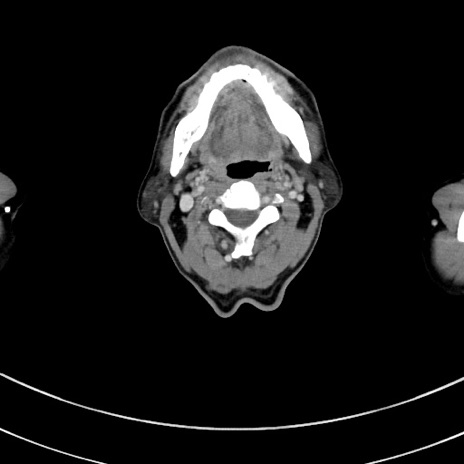

症例8(横断像)

【症例】 60歳代男性

【主訴】 黒色吐物

【現病歴】 4日前から嘔気自覚、2日前の朝食後にも嘔気あり、自分で手で嘔吐反射起こし嘔吐したところ血が混ざっていたため受診。

【既往歴】 5年前汎発性腹膜炎を伴う急性虫垂炎で手術、高血圧、前立腺肥大症、高脂血症

【身体所見】 腹部正中に手術癩痕あり 腹部平坦・軟圧痛なし膨満感あり

【データ】WBC 8400、CRP 4.54